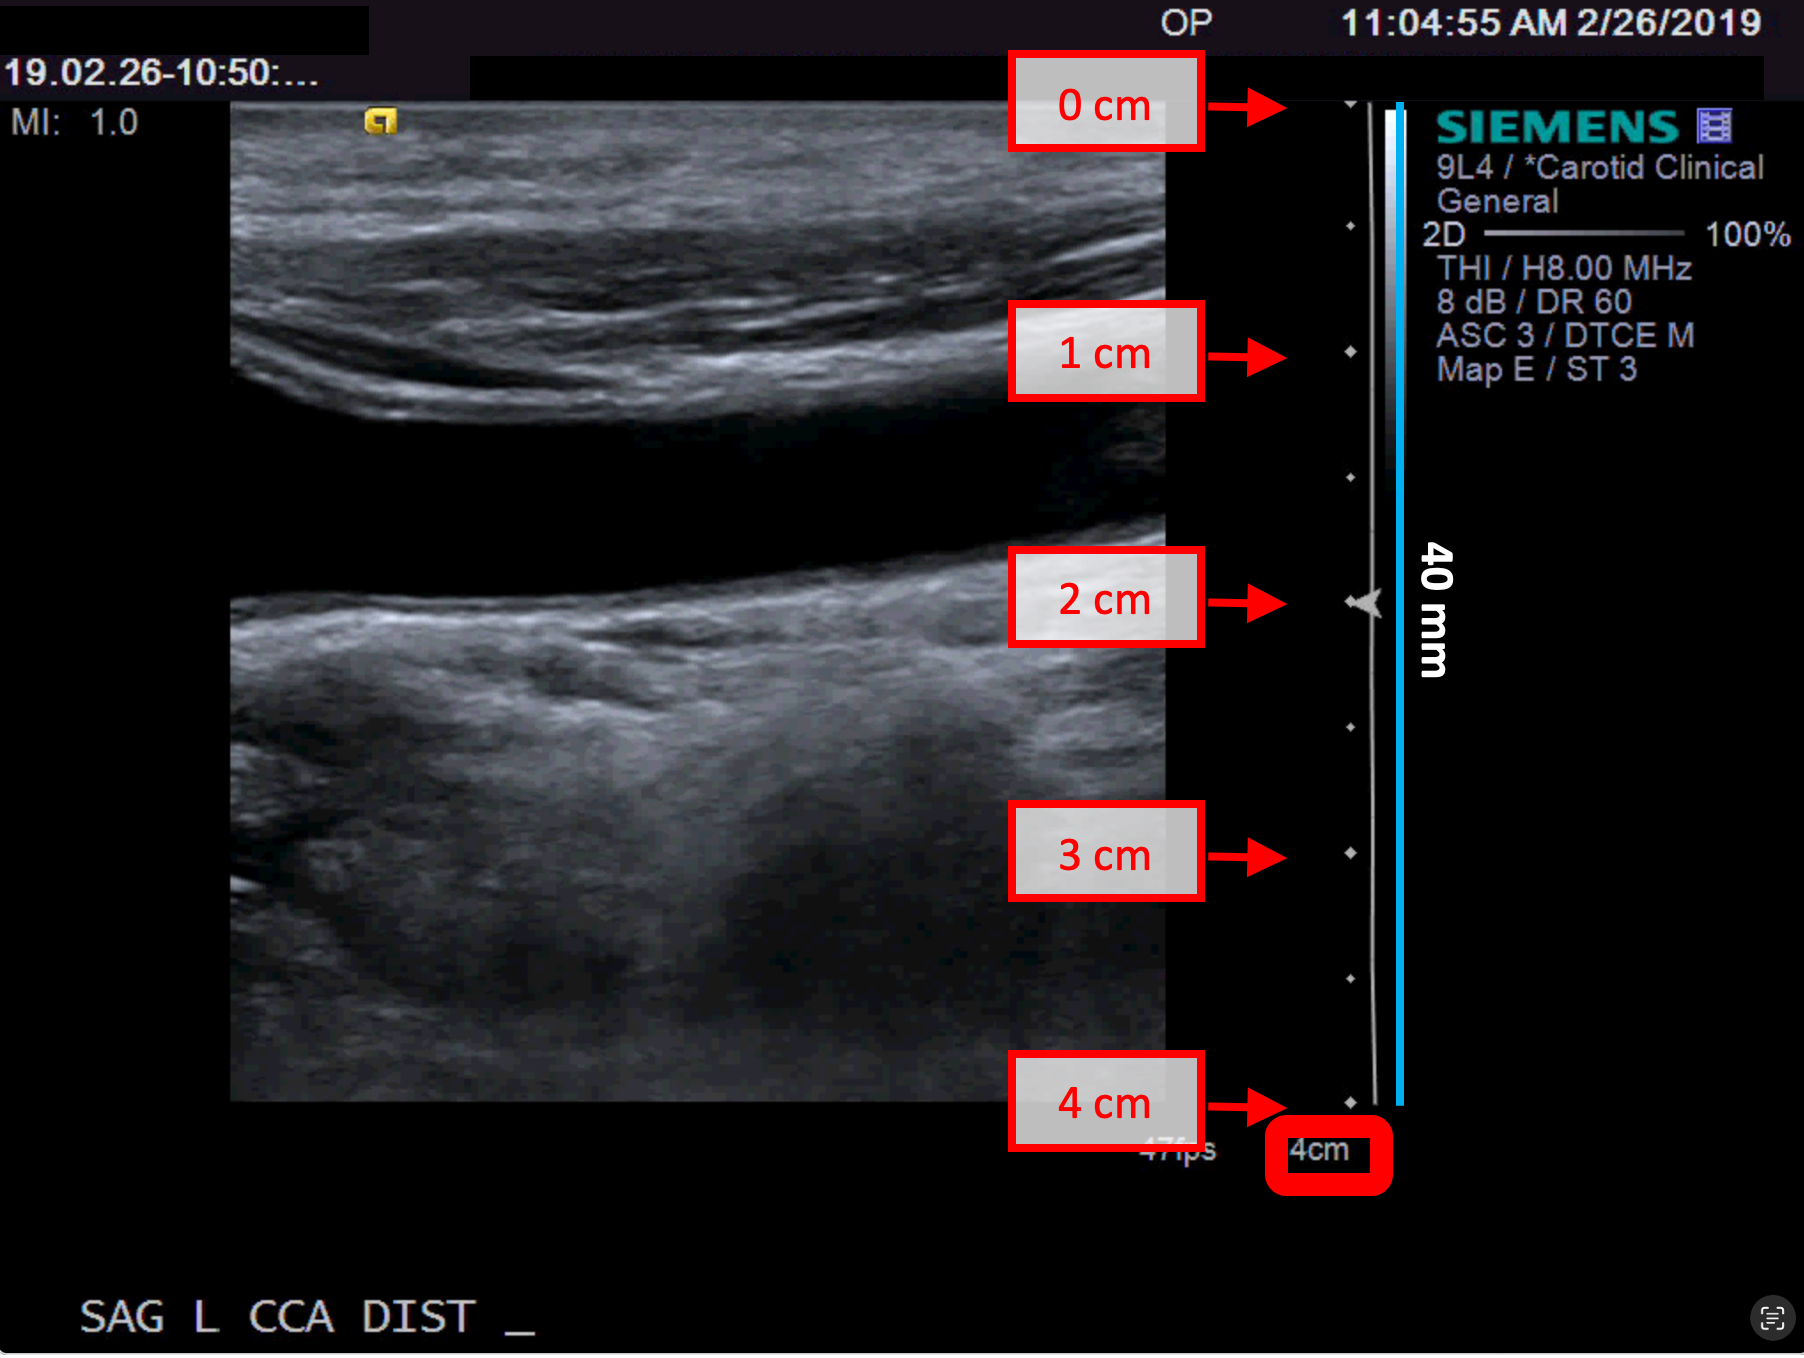

Exemples d'étalonnage en mode B

Les images suivantes présentent des exemples d'étalonnage de l'image en mode B. Les éléments graphiques en rouge indiquent où trouver les informations relatives à la profondeur de l'image échographique.